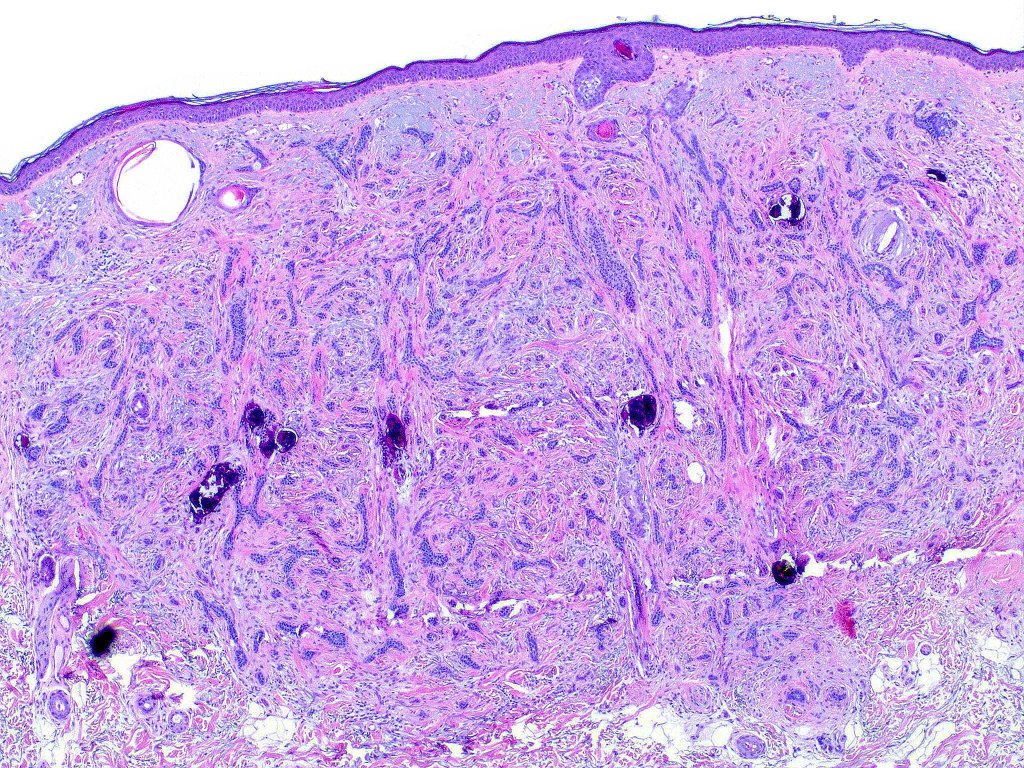

Histological features

•Consists of narrow epithelial strands & keratocysts embedded in a dense stroma

•Generally involves superficial & mid dermis but does not extend into the subcutaneous fat

•Calcification, foreign body giant cell reaction to keratin & bone are inconstant findings

•Perineural infiltration is documented but is exceptional & makes differentiation from MAC difficult